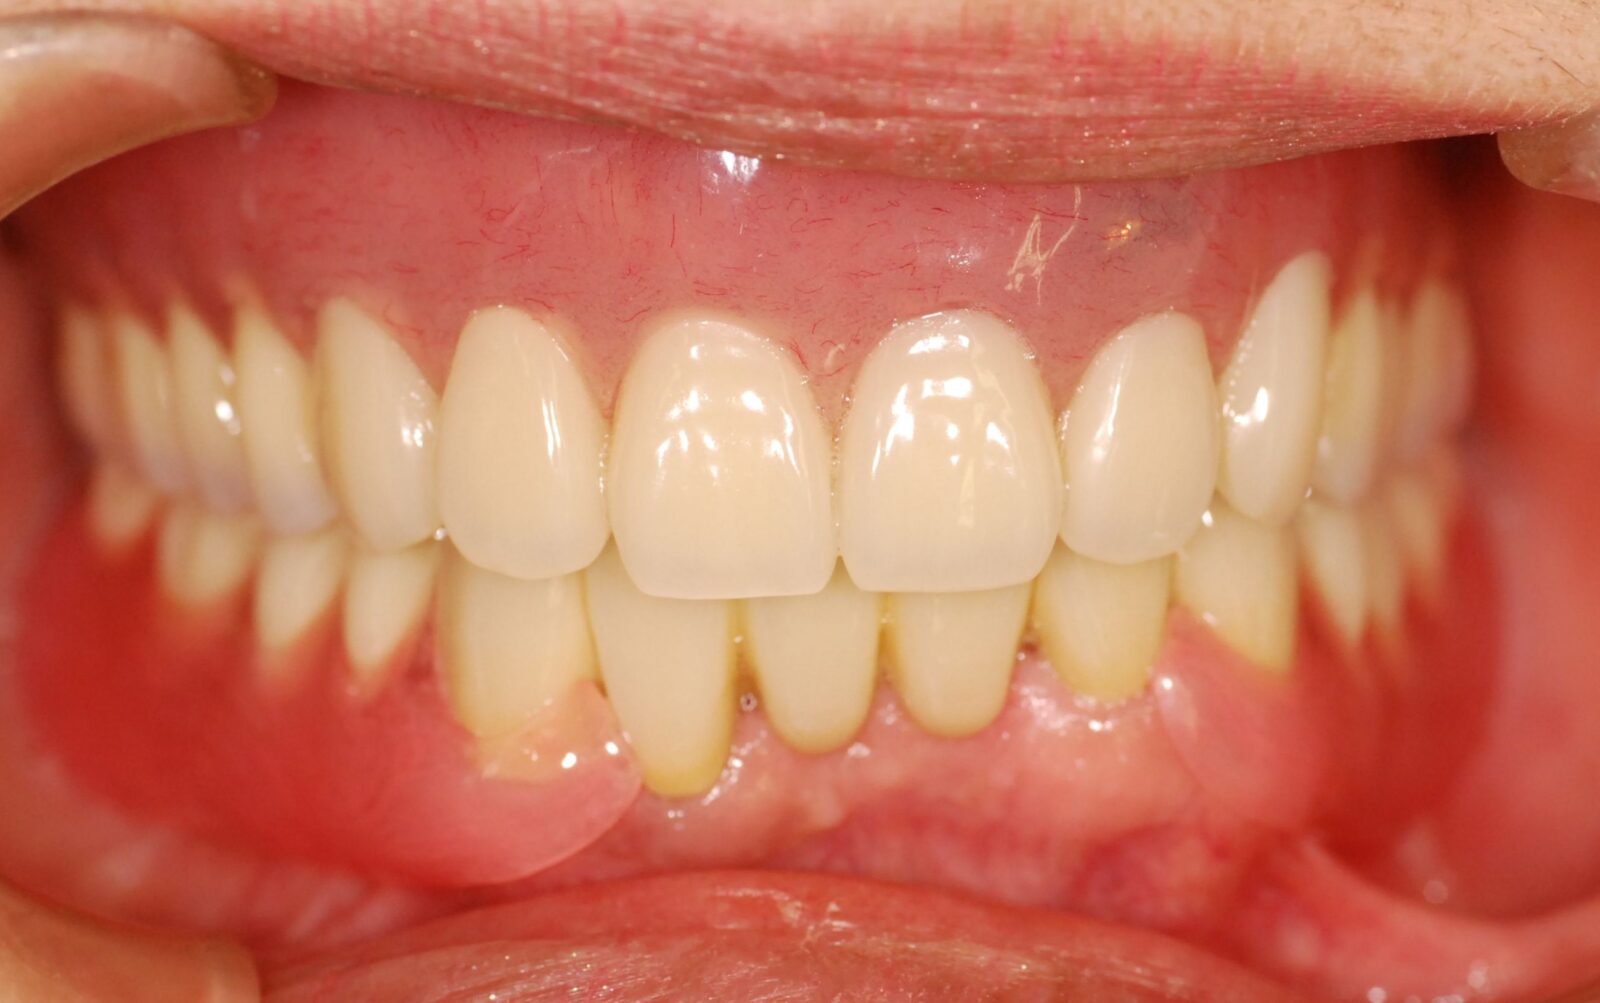

また、治療後の口元の状態が次の画像になります。

とても自然な口元になっています。